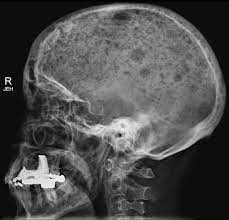

} myeloma cells produce paraproteins which are found in blood and urine (protein bence jones). The pelvis contains numerous lytic lesions without reactive sclerosis which have multiple myeloma. Healthy plasma cells help you fight infections by making antibodies that recognize and attack germs. Spotlight revised international staging system for multiple myeloma: Multiple myeloma is a cancer of plasma cells, which are white blood cells found mainly in the bone marrow. If you still can't find it, please let us know so we can add it!. Other tests include blood monoclonal immunoglobulin and radiology tests to determine the extent of bone lesions. Multiple myeloma is the second most common type of blood cancer after leukemia. 1,2,3 it accounts for approximately 1% of all malignant. Treatment response, detection of relapse. International myeloma working group molecular classification of multiple myeloma: It accounts for approximately 10% of all. Extraosseous myeloma refers to any manifestation of multiple myeloma where there is plasma cell proliferation outside the atypical manifestations of multiple myeloma:

Multiple myeloma is a cancer of plasma cells, which are white blood cells found mainly in the bone marrow. Find more information on clinical trials that are open for enrollment at mount sinai's center for excellence for multiple myeloma. Multiple myeloma (mm), also known as plasma cell myeloma and simply myeloma, is a cancer of plasma cells, a type of white blood cell that normally produces antibodies. Treatment response, detection of relapse. Related online courses on physioplus. 16,000 new cases and 11,000 deaths. Changing the treatment landscape for hematologic malignancies learn more. In multiple myeloma, when the cancer protein level is up, the normal antibody levels are down. If you still can't find it, please let us know so we can add it!. Tell the radiologist or the radiology technician about your diagnosis before receiving dye injection into. It accounts for approximately 10% of all. Other tests include blood monoclonal immunoglobulin and radiology tests to determine the extent of bone lesions. Spotlight revised international staging system for multiple myeloma: